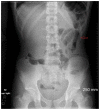

Burkitt lymphoma is a highly aggressive form of Non-Hodgkin lymphoma that responds favorably if diagnosed accurately and treated early. Recognition of the various radiologic manifestations of Burkitt lymphoma can help guide the clinician to expedite appropriate chemotherapy. We present two cases that illustrate different radiologic presentations of this aggressive gastrointestinal malignancy in children. Case 1 features a 7-year-old boy who presented to our hospital with recurrent ileocecal intussusception. Case 2 describes a 16-year-old male with history of blood-streaked stools. Ileocectomy was performed in both cases and histologic analysis showed the "starry sky pattern" and t(8;14) translocation, classic for Burkitt lymphoma. Both patients remain disease-free following surgical excision and chemotherapy.